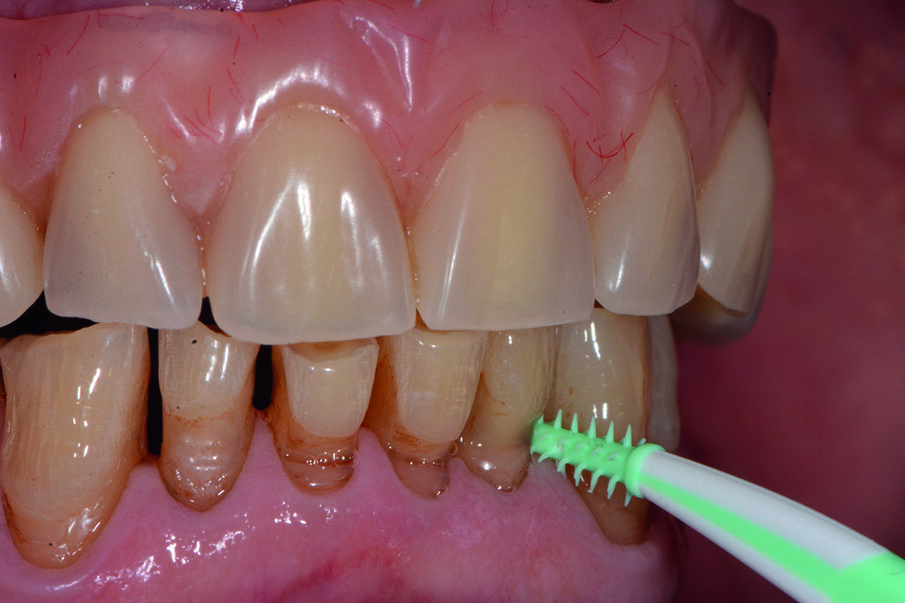

Documentiamo fotograficamente il cavo orale. Abbiamo mostrato al paziente, in real time, al fine di motivarlo a un più efficace controllo di placca domiciliare, i siti maggiormente interessati dall’accumulo di placca nel cavo orale, compresi, il dorso della lingua e gli spazi interprossimali e la barra implantare con l’aiuto del rilevatore di placca alla fluorescina Plac-o-Tect (Directa) (Fig. 10). Scegliamo per il paziente l’utilizzo corretto degli strumenti di igiene orale domiciliare – spazzolino e scovolino – più idonei alle sue esigenze strutturali, tissutali e anatomiche, alla manualità e alla predisposizione caratteriale alle differenti tecnologie manuali o meccaniche, come da tailored brushing method (Nardi et al., J Biomed, 2016).

Per implementare l’igiene nelle zone interdentali abbiamo indicato l’uso scovolino in gomma GUM® Soft-Picks® Advanced (Fig.11a), imbibito di dentifricio Implaclean (Fig. 11b). Il paziente riferisce di avere difficoltà con l’igiene della lingua, e quindi condividiamo la necessità di implementare l’igiene domiciliare con l’uso di un nettalingua (Fig. 12a) e 5 ml per qualche minuto 2-3 volte die di Riocol collutorio a base di soli estratti naturali (Fig. 12b), per le diverse azioni benefiche a vantaggio della mucosa orale. Abbiamo riferito al paziente che non pigmenta le superfici dentali grazie alla metodica di pura estrazione naturale dei componenti (lapacho, malva, piantaggine, camomilla) e acido ialuronico, efficace per le infiammazioni.